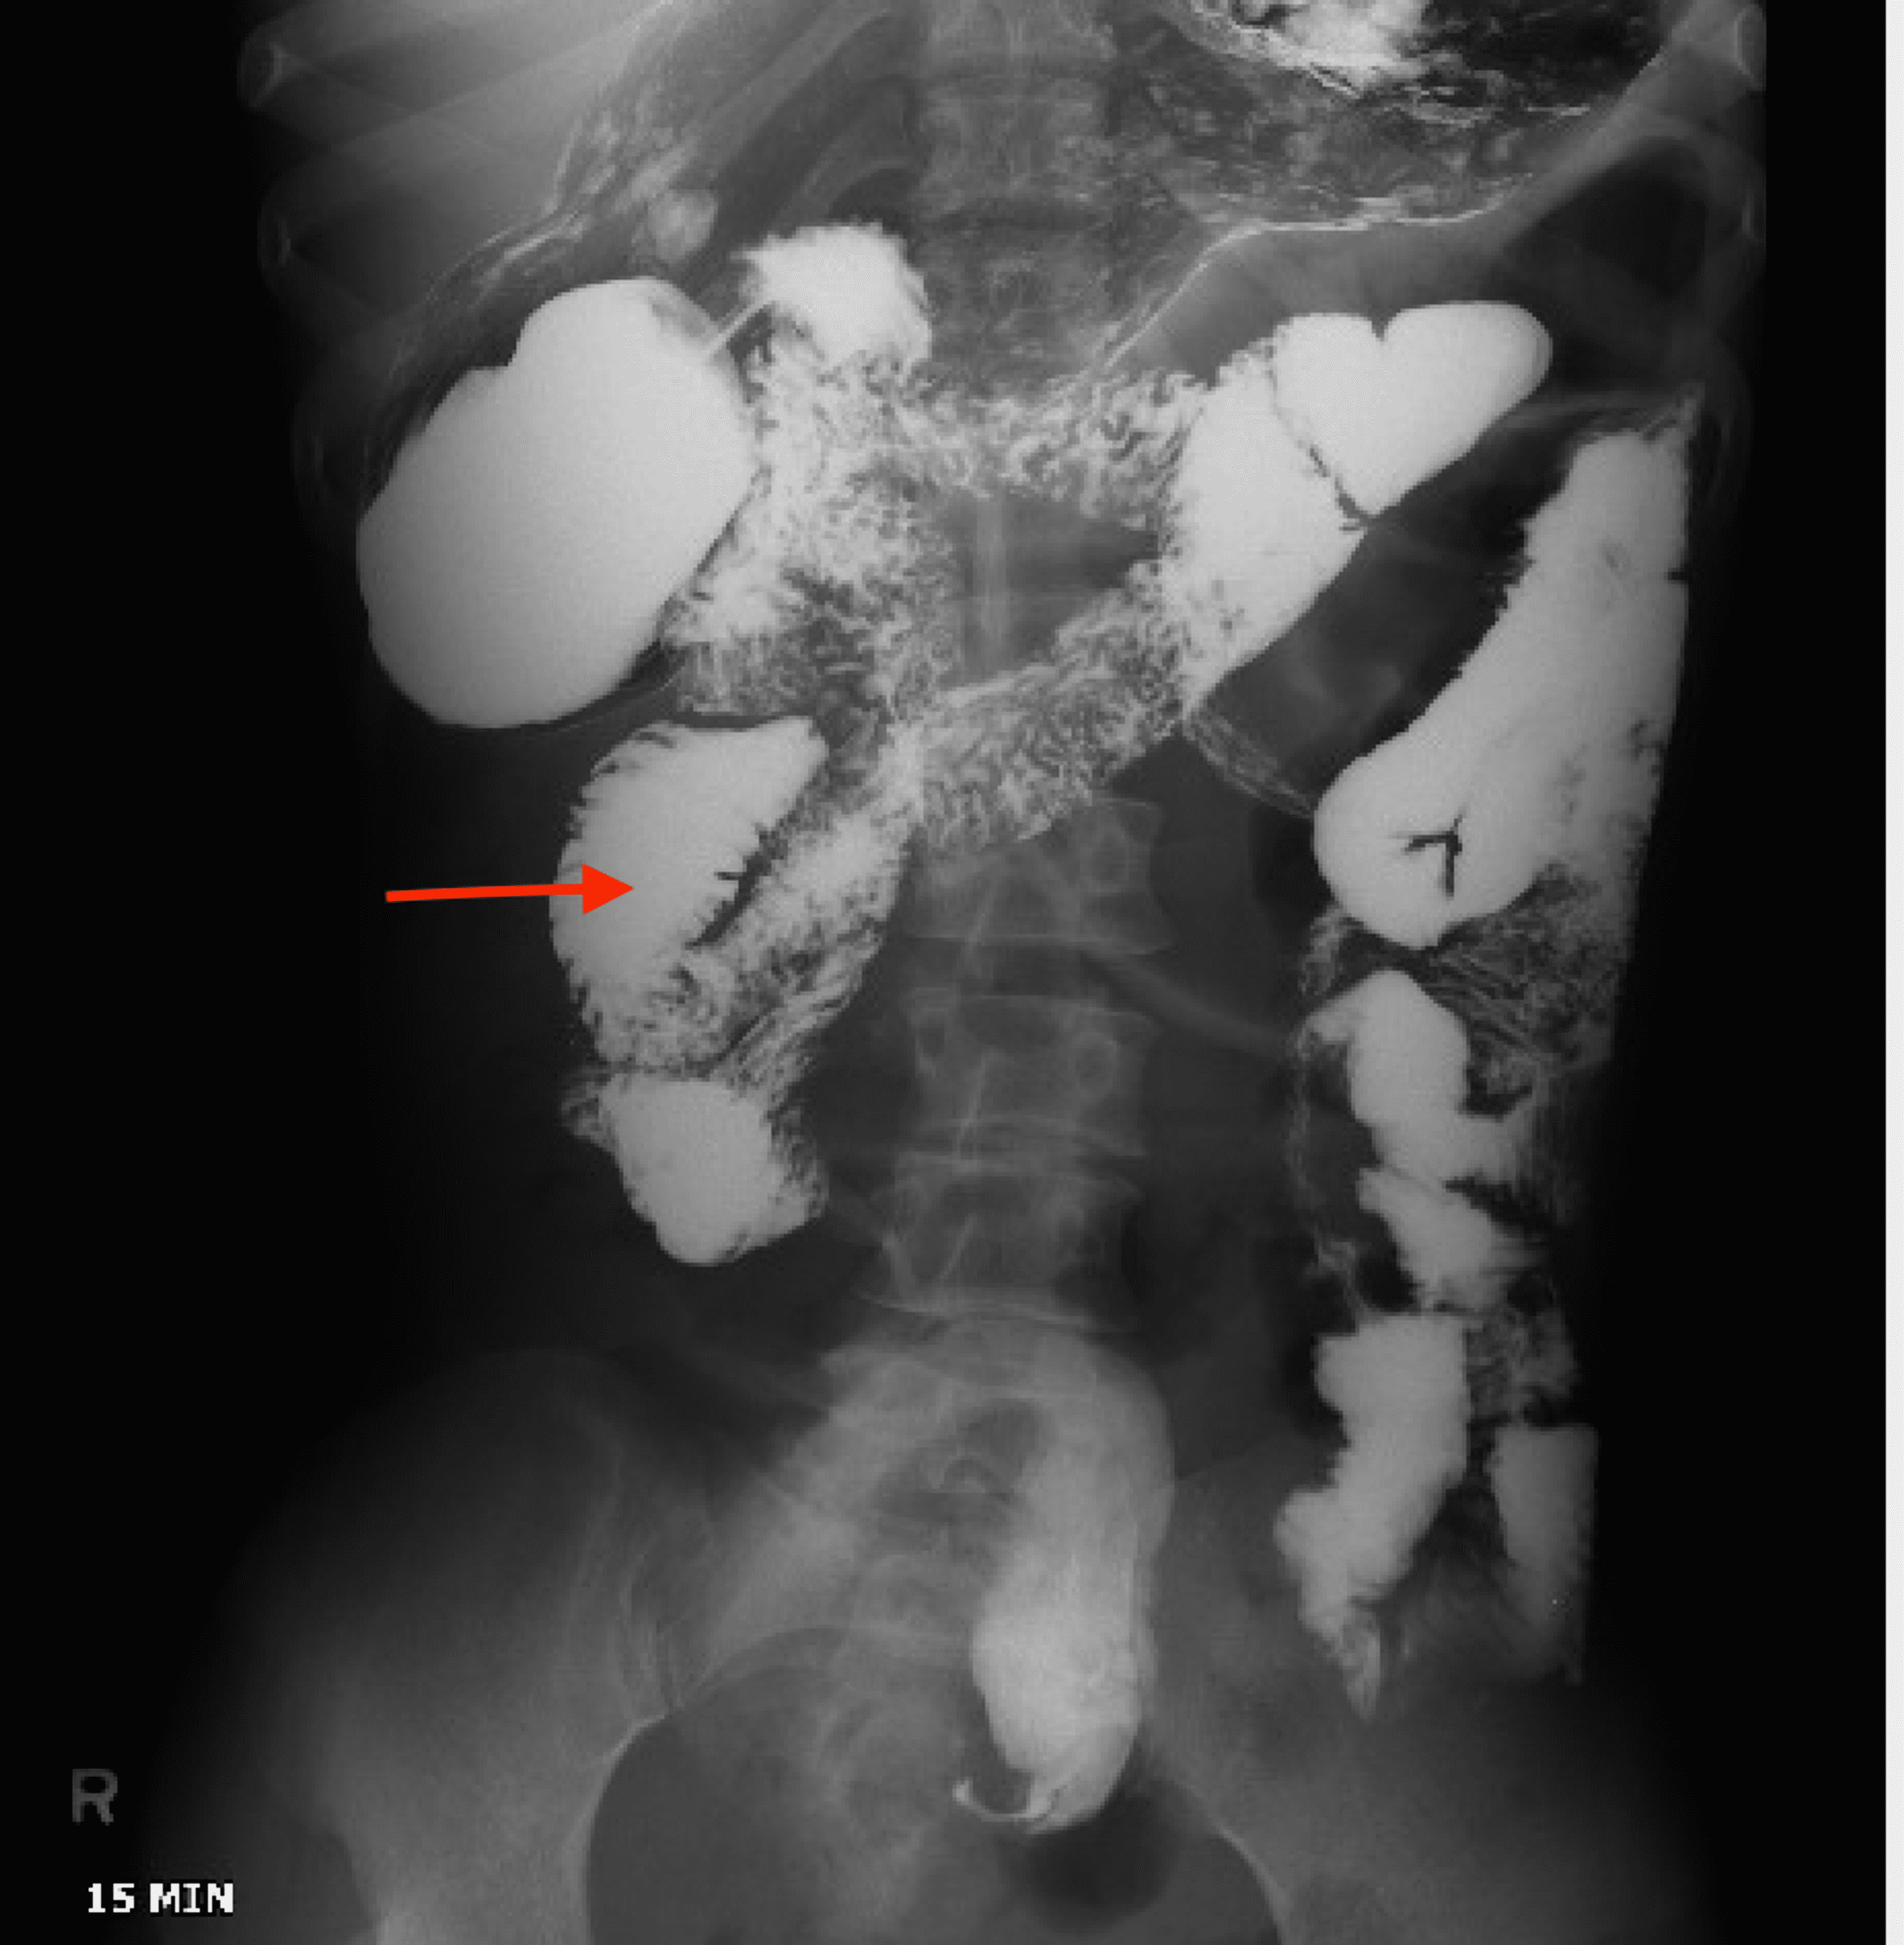

From radiologycases.my

Ischaemic colitis Radiology Cases Ischemic Colitis Fatal Symptoms are left lower quadrant pain and rectal bleeding. If you have ischemic colitis along with pain on your right side, or sudden belly pain that’s so severe you can’t find a comfortable position, head to. The colon receives less blood flow than any other portion of the. Less commonly, it can be a more serious problem. The prognosis of. Ischemic Colitis Fatal.

From www.semanticscholar.org

Figure 1 from Recurrent ischemic colitis in a patient with leiden factor V mutation and systemic Ischemic Colitis Fatal Some people have repeat or chronic episodes of ischemic colitis in one. The prognosis of patients with nomi or ischemic colitis depends on the etiology, severity, and distribution of the disease. If you have ischemic colitis along with pain on your right side, or sudden belly pain that’s so severe you can’t find a comfortable position, head to. The colon. Ischemic Colitis Fatal.